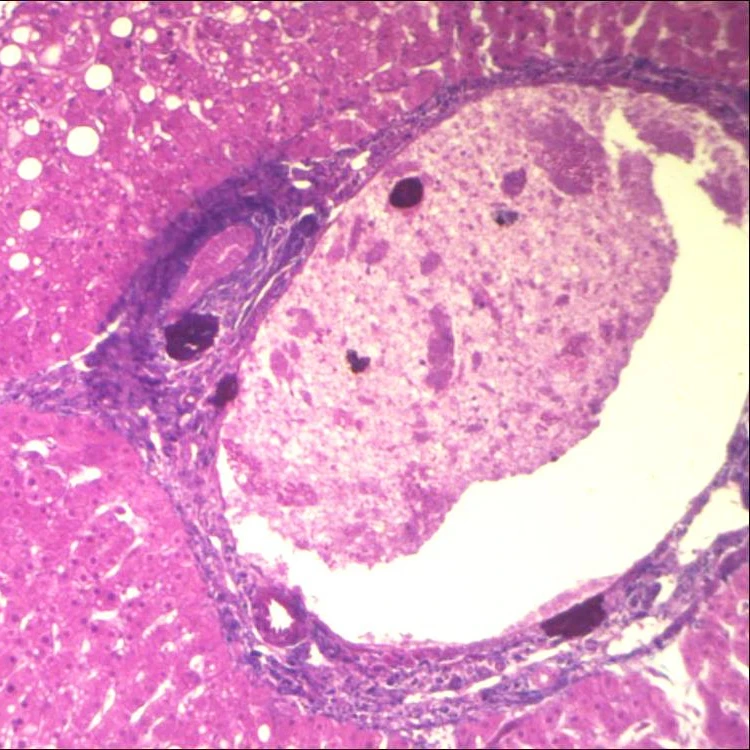

Cryptosporidium oocyst W.M.